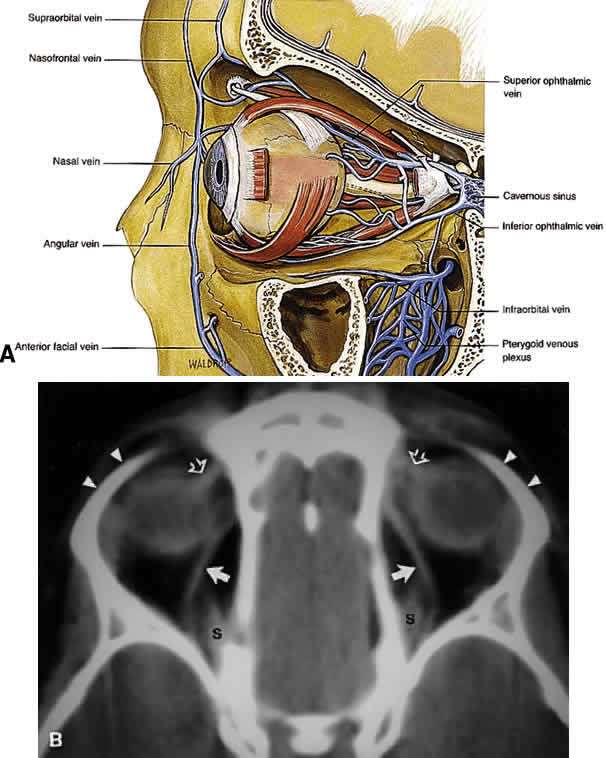

Veins Within the soft tissue of the orbit, venous drainage is distinctly separate from the arterial supply; a similar arrangement is found intracranially. Although the veins are found in a relatively reproducible pattern within the orbital septal system, the arteries travel more haphazardly within orbital fat.18 All orbital veins are valveless; this may facilitate more rapid posterior spread of infectious processes within the anterior orbit. The major venous drainage of the orbit is the superior ophthalmic vein and the CS (Fig. 21). The superior ophthalmic vein follows a medial-to-lateral route posteriorly along the superior orbit, tethered beneath the superior rectus muscle by a fascial sling.19 At the orbital apex, it is usually joined by the inferior ophthalmic vein, which also communicates through more minor branches with the pterygopalatine plexus through the IOF. The central retinal vein typically drains directly into the CS without joining the superior ophthalmic vein. Anteriorly, the orbit also drains into the angular vein of the facial plexus. Lymphatics To date, no lymphatic system has been identified within the human orbit, although recent studies that identified lymphatic drainage in primate orbits make this an intriguing possibility.20 In the eyelids, lymphatic drainage occurs through a deep (posterior lamellar) and superficial (anterior lamellar) system. The medial aspect of the eyelids drains into the submandibular lymph nodes, whereas the lateral aspect and most of the upper eyelid drain into the preauricular and parotid nodes. EXTRAOCULAR MUSCLES AND ORBITAL FASCIAL SYSTEM The EOMs insert 5.5 to 8 mm behind the limbus of the globe. Specific details regarding the dimensions and functions of each EOM are found elsewhere. Useful points are summarized in Table 6. The EOMs are striated and composed of aerobic, twitch-type Fibrillenstruktur fibers and anaerobic, tonic-type Felderstruktur fibers.36,37 The most common affliction of the EOMs is inflammatory myositis, which is seen most typically in thyroid-related orbitopathy and idiopathic inflammatory pseudotumor. Rhabdomyosarcoma, a tumor with focal striated muscle differentiation that generally occurs in children, appears to arise from indifferent orbital mesenchyme rather than from preformed and completely differentiated striated muscle fibers. Landmark anatomic investigations by Koornneef38–40 have shown that there are highly elaborate and reproducible connections of the epimysium of the EOMs with the fibrous connective tissue system of the orbital fat, the epibulbar fascia of Tenon's capsule, and the periosteum (periorbita) (Fig. 22). This extensive yet reproducible network of connective tissue provides support for the delicate neurovascular structures traversing the orbit, both facilitates and restricts the movement of EOMs in a coordinated fashion, and compartmentalizes the orbit into various spaces. Because of the inherent complexity of the orbital connective tissue system, any disruption in one area of the orbit may cause significant dysfunction of more distant areas. For example, these connections become clinically important in the understanding of restricted motility after orbital wall fracture and orbital decompressions for Graves' orbitopathy, as well as the superior sulcus and lower eyelid deformities that follow enucleation and orbital implant placement. To promote a clearer understanding, Dutton has succinctly summarized the orbital connective tissue system by dividing it into three components: Tenon's capsule, the anterior orbital suspensory system, and the posterior orbital suspensory system.41 The three components should not be considered as distinct anatomic entities, because complex attachments unite this triad into one comprehensive unit. Tenon's capsule begins anteriorly just posterior to the limbus with firm attachments to the underlying episclera, investing the globe in an elastic and vascular connective tissue cover. The capsule also encompasses the anterior portions of the EOMs. Posteriorly, Tenon's capsule surrounds the optic nerve, interdigitating with the dural sheath. Other than its anterior and posterior attachments to the globe, Tenon's capsule is only loosely adherent to the underlying sclera, thereby cushioning the movement of the globe. An intermuscular fibrous membrane connects the four rectus muscles around the globe to create a distinct intraconal space, but in the deeper orbital tissues this membranous system is not complete, so that the distinction between a central and a peripheral orbital space is lost toward the orbital apex. Anteriorly, the intermuscular fibers also blend with Tenon's capsule, creating a sort of rotating sleeve around the globe during ocular rotations. The anterior orbital suspensory system is primarily concerned with providing support for the globe and fixation for eyelid structures. In addition, fascial support exists for the lacrimal gland (Sommering's ligaments) and the superior oblique muscle in the area of the trochlea. The four main structures of the anterior system are Whitnall's suspensory ligament, Lockwood's ligament, and the medial and lateral canthal tendons. These structures are discussed in detail elsewhere. The anterior suspensory system also provides anchoring points for the check ligaments of the EOMs, limiting their overaction during ocular rotations. As already noted, the orbital septal system becomes less defined more posteriorly. The well-defined intraconal space encountered anteriorly blends with the surrounding extraconal space as one approaches the orbital apex. The annulus of Zinn, discussed earlier, forms dense adhesions to the periosteum of the orbital apex around the optic canal and SOF (see Fig. 12). In addition, fibers pass inferiorly along the IOF to interdigitate with Müller's orbital muscle, which spans the fissure. As the levator palpebrae superioris (levator) muscle and superior rectus muscle course anteriorly, diffuse connections form to the orbital roof, creating an effective suspensory system. Further, diffuse fascial connections form between the levator and superior rectus muscles, allowing precise coordination of upper eyelid retraction with upgaze. Note that on imaging studies, the close association of these two muscles often makes them look like a single anatomic unit; the term “levator-superior rectus complex”is often found in radiologic reports (see Fig. 17). A fascial sling forms beneath the superior rectus muscle to provide suspensory support for the superior ophthalmic vein. The medial rectus muscle has few important attachments to the posterior medial orbital wall, in contrast to the lateral rectus muscle, which has diffuse attachments to the lateral orbital wall from the lateral canthal tendon anteriorly to the annulus of Zinn posteriorly. Presumably, the extensive fascial attachments of the lateral rectus muscle sheath provide a firm attachment sleeve within which the lateral rectus muscle can function while still subtending a significant arc around the globe.41 The orbital muscle of Müller spans the IOF, separating the orbit from the pterygopalatine fossa below. The function of this smooth muscle in humans is unclear. It may simply represent an anatomic relic of evolution: Dutton notes that the orbital floor in lower mammals is poorly defined posteriorly and in need of muscular support.41 Some anatomists also ascribe a vasculosympathetic function to the muscle, given its proximity to the inferior ophthalmic vein. LACRIMAL SYSTEM Drainage System Drainage of tears from the eyelids into the nose requires a patent drainage system (Fig. 23) comprising the puncta, canaliculi, lacrimal sac, and nasolacrimal duct, proper positioning of the eyelids against the globe, and an intact lacrimal pump function.42,43 If any of these components fails, epiphora will result. The puncta are defined as the openings of the canaliculi onto the eyelid margin (see Fig. 6). Each punctum measures about 0.3 mm in diameter and is found 0.5 to 1.0 mm medial to the end of the tarsal plate. The upper punctum is usually found slightly nasal to the lower punctum, each measuring 6 mm and 6.5 mm from the medial commissure, respectively. Thus, the puncta do not overlap each other during eyelid blink. Peripunctal tissue is avascular and rich in elastic tissue. This last point is documented clinically when observing the rapid collapse of the puncta in younger patients immediately after probing. The canaliculi begin anatomically at the puncta. The vertical portion measures about 2 mm, with an ampulla (2.5 mm in diameter) forming just beneath the punctal opening. The horizontal portion measures 8 mm in length, surrounded by the medial portions of the muscle of Riolan (also known as Horner's muscle, an extension of the pretarsal orbicularis) and traveling through the fiber network of the medial canthal tendon. The diameter of each canaliculus is only 1 mm. In more than 90% of individuals, the canaliculi join to form a common canaliculus known as the ampulla of Maier, which then enters the lacrimal sac at the common internal punctum. The common internal punctum forms the first major valve of the lacrimal system, the valve of Rosenmuller, and acts to prevent reflux of tears back into the canaliculi during lacrimal pump function. The lacrimal sac is found within its bony fossa, formed by the anterior and posterior lacrimal crests (see Fig. 7A and B). It measures 12 to 15 mm in length and has strong attachments over its lateral surface from the medial canthal tendon and fibers of the orbicularis (Horner's and Jones' muscles). The portion of the sac found above the medial canthal tendon is defined as the fundus, measuring 3 to 5 mm in height. Inferiorly, the sac opens into the nasolacrimal duct at the lacrimal ostium. (Note the proximity of the inferior oblique muscle origin, an important consideration during surgery of the lacrimal sac.) The pseudostratified nonkeratinized columnar epithelium of the lacrimal sac is thrown into numerous folds that form a screwlike passageway for tear outflow. Although each fold has been given various eponyms (see Fig. 23B), these are not important to remember; rather, understand that the folds as a unit perform the important function of efficiently driving tear flow in a unilateral direction down the nasolacrimal duct. The walls of the sac are rich in elastic tissue, thereby allowing for the constant collapse and reformation of the sac during the blink reflex. The nasolacrimal duct travels within its canal for 12 mm through the nasofrontal process of the maxillary bone, opening intranasally into the inferior meatus, found just beneath the inferior turbinate. The opening of the nasolacrimal duct is about 16 to 25 mm posterior to the tip of the nose in adults, and about half that distance in children. The duct travels in a posterior and lateral direction,24 angulating 15° and 5°, respectively. As already noted, the inferior opening of the duct is defined as the valve of Hasner. The lacrimal pump mechanism is described elsewhere. In addition to the dynamic process of the pump, gravity also assists in tear outflow. SECRETORY SYSTEM The aqueous portion of the tear film is produced by several glandular units found within the eyelids and anterior orbit. Considerable controversy exists regarding the innervation and contribution of each set of glands.28 One theory put forth by Jones defines the main lacrimal gland as a “reflex”secretor (i.e., dependent on neural stimulation for tear production), whereas the accessory lacrimal glands found along the inner aspect of the eyelids are called “basic”secretors, producing tears at a constant, unchanging rate.29 This theory forms the basis for the Schirmer tests of tear production. In the fully developed orbit, the lacrimal gland is normally impalpable and is situated in a small fossa behind the superotemporal orbital rim. It is not an encapsulated structure but rather is an aggregated collection of lobules of secretory tissue set in the superotemporal orbital fat, with interlobular ducts converging into the main excretory ducts in the superotemporal fornix. Within the secretory acini are located inner columnar to cuboidal zymogen-bearing cells, on the outer aspect of which are applied contractile myoepithelial cells. Mucus-producing elements are not present. Myoepithelial cells are not present in the terminal intralobular ductules or in the interlobular ducts. The acinar elements are not capable of regenerating after inflammatory insults, and the regenerative capacity of the gland resides in the terminal ductules. Lymphoid tissue is present in the substantia propria of the conjunctiva, and lymphocytes and plasma cells are lightly dispersed among the secretory acini of the lacrimal gland, but the deep orbital tissue is devoid of a standing population of lymphoid cells. Based on a study of the immunoarchitecture of the lacrimal gland using monoclonal antibodies as markers, plasma cells are the predominant mononuclear cell type, making up 54%, and are located in the interstitium of the gland. Immunoglobulin A (IgA) vastly predominates over other immunoglobulin types; lymphocytes of the substantia propria of the conjunctiva and of the lacrimal gland secrete IgA, which has a secretory piece added to it as it moves across the ducts of the gland or the conjunctival epithelium. T cells make up 40% of all mononuclear cells, with T8 suppressor/cytotoxic cells outnumbering T4 helper cells. Occasional small lymphoid aggregates without germinal centers may also be seen at the juncture of intralobular and interlobular ducts, in which T4 helper cells predominate and a smattering of B cells are found. Lymphoid tumors, representing reactive hyperplasias and true lymphomas, consequently are derived from blood-borne lymphocytes that emigrate from the orbital vascular system into the orbital connective tissues, generally into the orbital fat. To date, there are no identifiable endothelial-lined lymphatics within the orbit, although the lacrimal gland itself contains lymphatic channels that drain to the preauricular and cervical nodes. The fact that the lacrimal gland has a standing population of lymphocytes and plasma cells—which are not, however, organized into lymph nodes (as may be seen in the parotid gland)—may explain the relative frequency of the development of idiopathic dacryoadenitis and lymphoid tumors of the gland. Inflammatory pseudotumors, lymphoid tumors, inflammations such as sarcoidosis and Sjögren syndrome, and epithelial tumors are the main types of pathology that arise from or involve the lacrimal gland. The main lacrimal gland is split into two lobes, the palpebral and the orbital, by the lateral horn of the levator aponeurosis2 (Fig. 24). The palpebral lobe measures about one-third the volume of the orbital lobe, and its subconjunctival location is easily identified during slit-lamp examination. The orbital lobe lies within its fossa, a concavity found within the lateral portion of the orbital roof. Fibrous septa known as Sommering's ligaments run from the gland to attach it more firmly to the periosteum of the lacrimal gland fossa. Whitnall's ligament also adds support for lacrimal gland suspension.30 (The lacrimal sac fossa is distinctly separate from the lacrimal gland fossa; the term “lacrimal fossa”is discouraged because it is confusing in its nonspecificity.) The shape of the orbital lobe is rather like that of a pancake (see Fig. 21B). The orbital lobe is usually limited to its fossa, but it is not uncommon to encounter posterior tails of lacrimal gland tissue traveling toward the orbital apex on routine CT/MRI studies.1 Likewise, the palpebral lobe may extend as inferiorly as the lateral canthal tendon in some individuals.31 Tear outflow passes from the orbital to the palpebral lobe through the levator aponeurosis; aggressive dissection in this area during levator surgery can thus damage the outflow mechanism. The palpebral lobe opens into the superolateral conjunctival fornix through 10 to 12 ductules. Innervation to the lacrimal gland remains controversial32 but can be summarized succinctly as sensory innervation from the lacrimal nerve (V-1) and parasympathetic innervation from the pterygopalatine ganglion.23 The role of sympathetic innervation is not completely understood. The accessory lacrimal glands or basic secretors are usually grouped as the glands of Krause, found along the conjunctival fornices, and the glands of Wolfring, found along the superior tarsal border of the upper eyelid. The glands of Wolfring may be injured during ptosis repair by a posterior approach. The glands of Popov are located within the substance of the caruncle. Two additional components of the tear film are mentioned briefly. The outer lipid layer is produced by the meibomian glands, which form excavations within the tarsus and open at the eyelid margin (and by minor contributions from the glands of Zeis and Moll of the eyelash follicle). The inner mucin layer is made by the conjunctival goblet cells. |